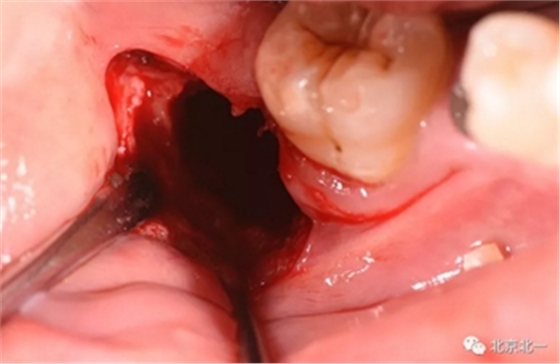

去骨:原则暴露最大周径线即可, 尽可能少去骨, 微创拔除。

截冠:有丝分裂至关重要。 保证微创下拔除智齿。

术后强调冲洗创口, 搔刮血液充盈。

有丝分裂拔牙技术展示

拔牙神器之一展示, 全程无菌。